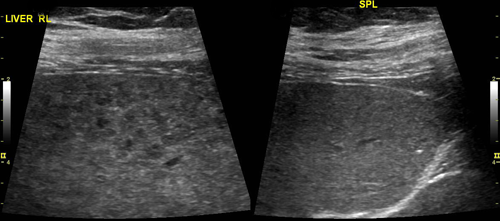

The UCSF ultrasound subspecialty performs the full array of ultrasound procedures, from general abdominal and fetal ultrasonography to the most advanced techniques, including color-flow doppler scans, ultrasonographically guided biopsies and aspirations, and endovaginal and endoscopic studies.

All UCSF ultrasonography facilities are equipped with the most up to date high resolution 2D, 3D, 4D grayscale and color-flow doppler scanning equipment.